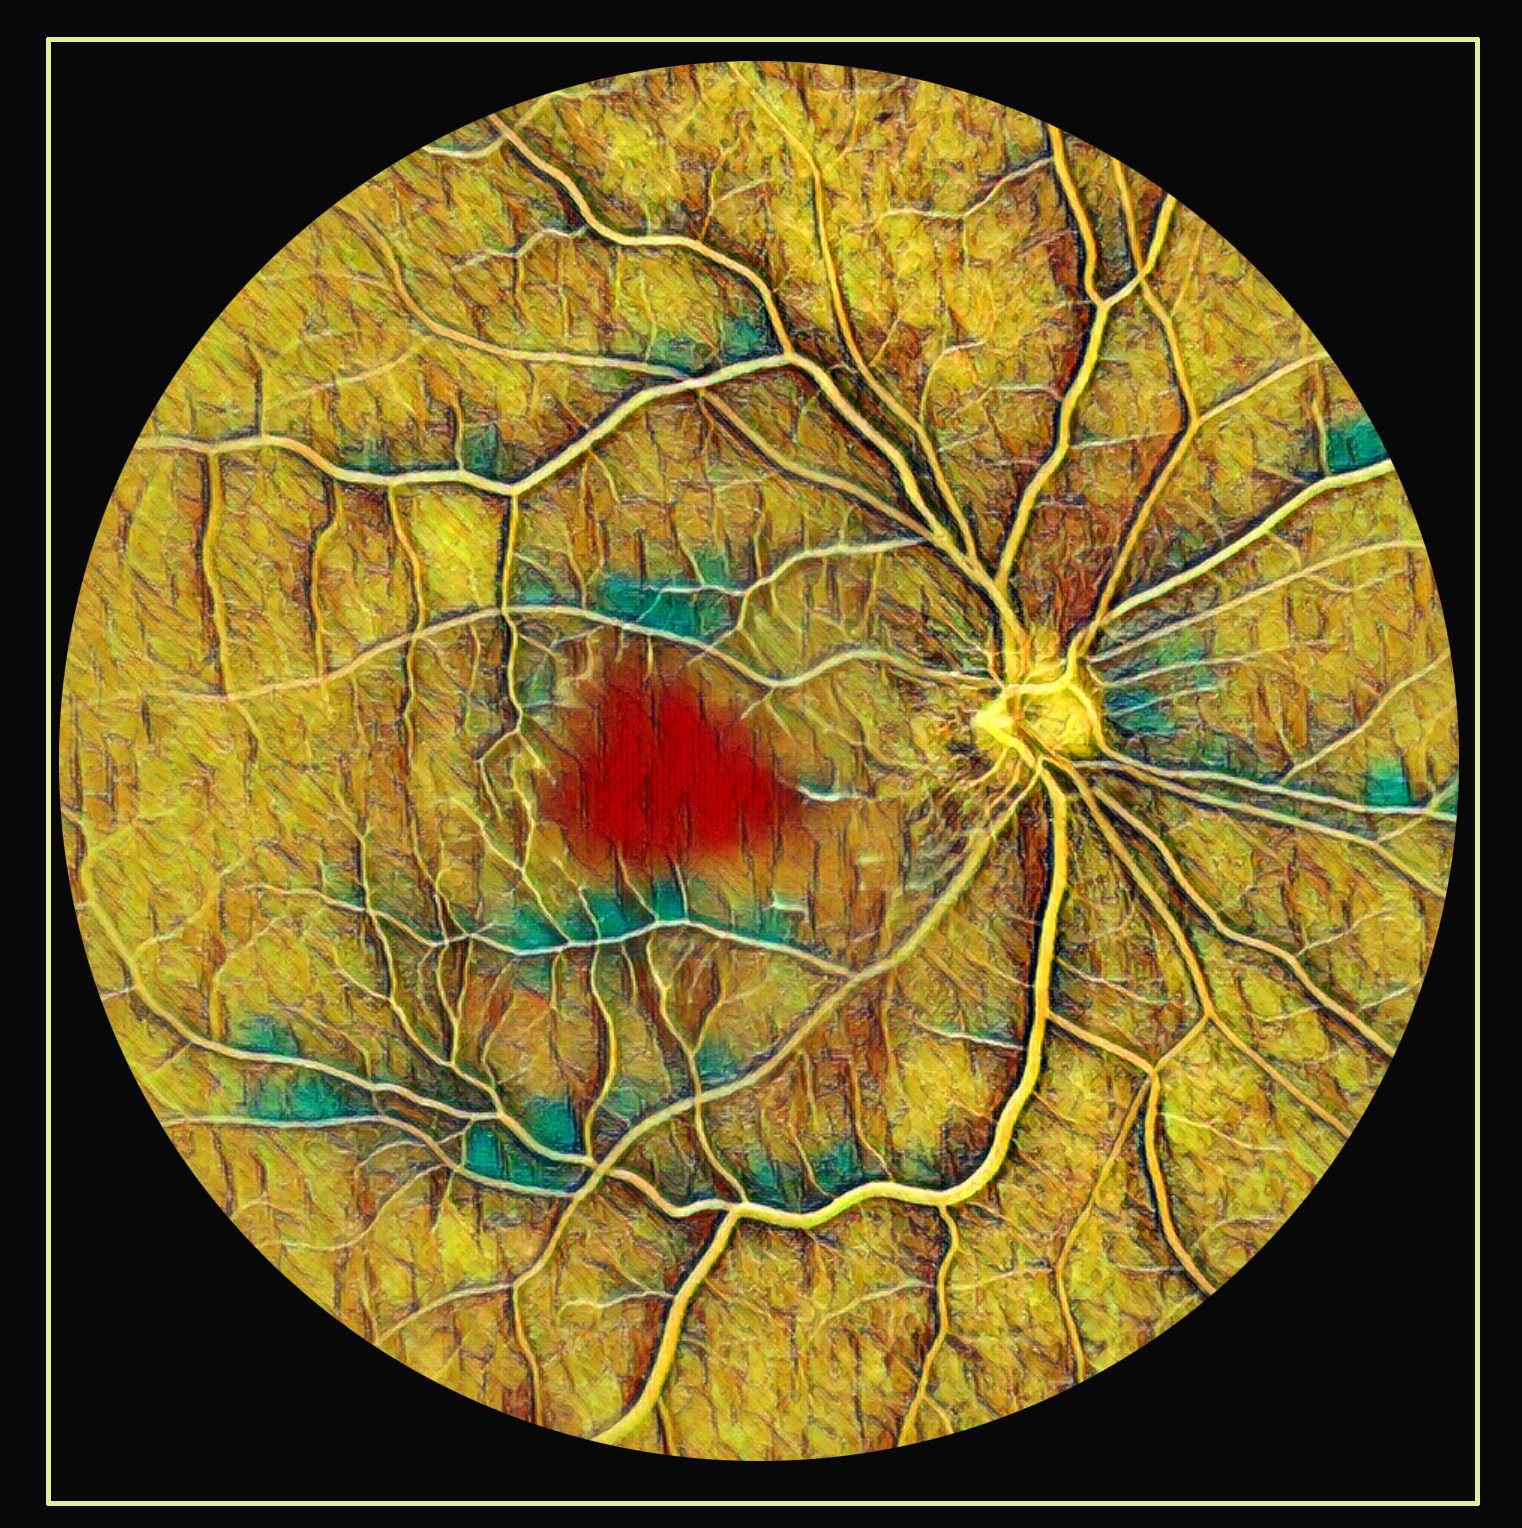

Watercolor CRAO Presented by Harold Rodriguez, OCT-C This photograph received Honorable Mention, The Eye As Art in the 2025 OPS Scientific Exhibit. Filed Under Retina OPS Photo